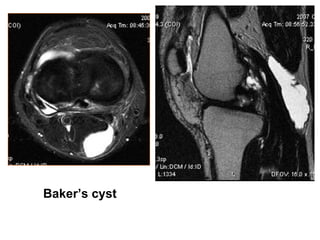

Baker’s cyst

VIEÂM BAO KHÔÙP GOÁI